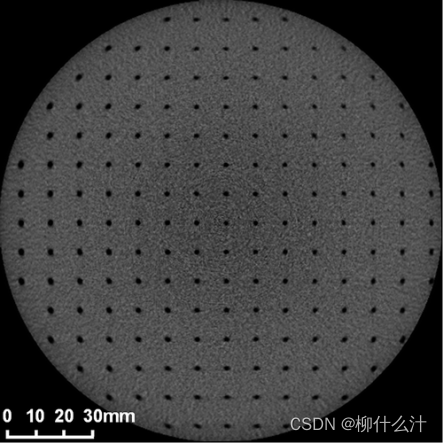

测试用的CBCT图像用于分析几何变形